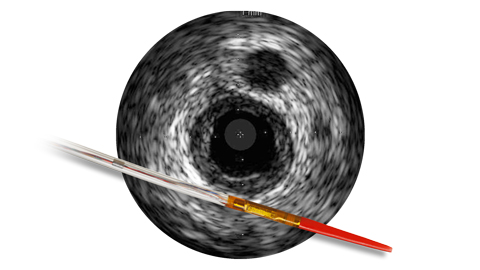

Ангиография дает сведения о характеристиках просвета сосуда, но не позволяет получить четкого изображения сосуда и поражения.

Между тем, использование ВСУЗИ помогает получить более четкую картину и улучшить результаты лечения пациента за счет планирования стентирования на основе данных и оптимизации стента после его установки1.